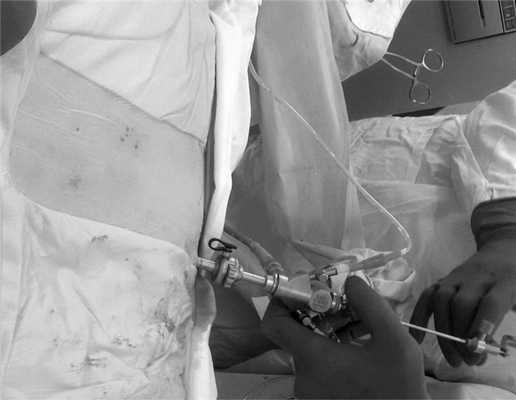

В нашей серии инвазивное крепление референсной рамки не использовалось. Референсная рамка укреплялась на стерильное операционное поле по средней линии в области поясничного отдела позвоночника или в ягодичной области на ипсилатеральной стороне доступа (рис. 3). После интеграции полученных КТ-изображений и в начале манипуляций, для предотвращения увеличения погрешности из-за смещения референсной рамки, рамку плотно фиксировали стерильной полиэтиленовой пленкой до укрепления светоотражающих шариков. Для этого использовалось стерильное полиэтиленовое поле фирмы «Opsite». После фиксации референсной рамки проводилась КТ с последующей интеграцией исследования на рабочую станцию S7, после интеграции одного из инструментов, используемых для доступа, рассчитывалась траектория проведения доступа (рис. 4).

Рис. 3. Вид установленной и фиксированной референсной рамки на коже пациента.